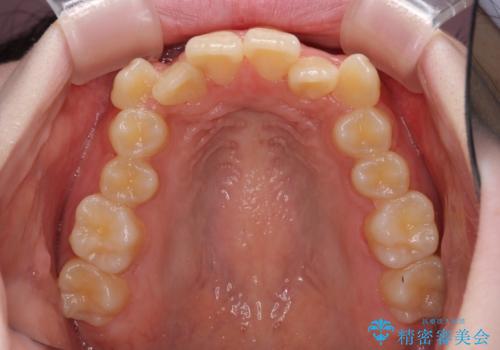

前歯の叢生は強かったのですが、口元が引っ込んでいる印象であったため、非抜歯にて矯正治療を行うこととしました。

治療途中で大学受験があり、来院できない時期がありましたが、2年以内で満足のいく歯並びを達成することができました。